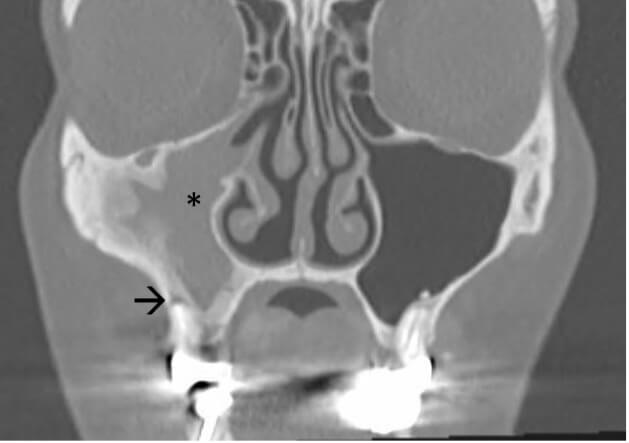

Fig. 4.

Computed tomography (CT) scan of a patient with infection of the right maxillary sinus (*) due to chronic apical periodontitis localized on a root (arrow) of tooth #16.